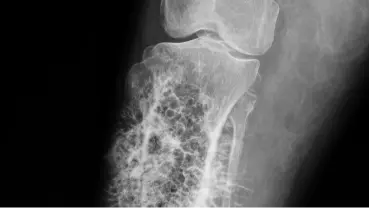

Estudios de imagen esenciales

Los estudios de imagen son el pilar del diagnóstico del cáncer de hueso, ya que permiten visualizar los huesos y detectar cualquier anomalía. Estos son a menudo los primeros exámenes que se realizan cuando se sospecha la enfermedad.

Estos estudios no solo revelan la presencia de un tumor, sino también su tamaño, forma, y si ha afectado los tejidos circundantes, lo cual es de un valor elevado para la estadificación inicial de la enfermedad.

Radiografías, resonancia y tomografía

Las radiografías suelen ser la primera prueba de imagen, mostrando cambios en la densidad ósea o la presencia de una masa. Le siguen la resonancia magnética (RM), que proporciona imágenes detalladas de los tejidos blandos y la médula ósea, y la tomografía computarizada (TC), que ofrece cortes transversales precisos del hueso y los tejidos adyacentes.